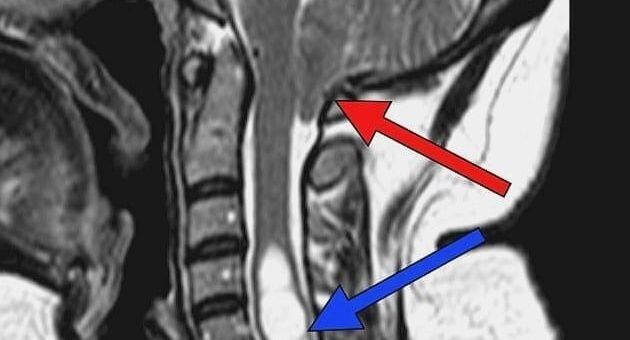

МРТ: красная стрелка показывает опущение миндаликов мозжечка ниже большого затылочного отверстия / Пресс-служба Долгопрудненской больницы

Магнитно-резонансная томография показала, что у женщины аномалия Киари, при которой мозжечковые миндалины опускаются ниже большого затылочного отверстия. Также у нее выявили кисту. Отсутствие терапии со временем могло привести к атрофии мышц кистей, проблемам с глотанием, гидроцефалии и даже внезапной смерти.